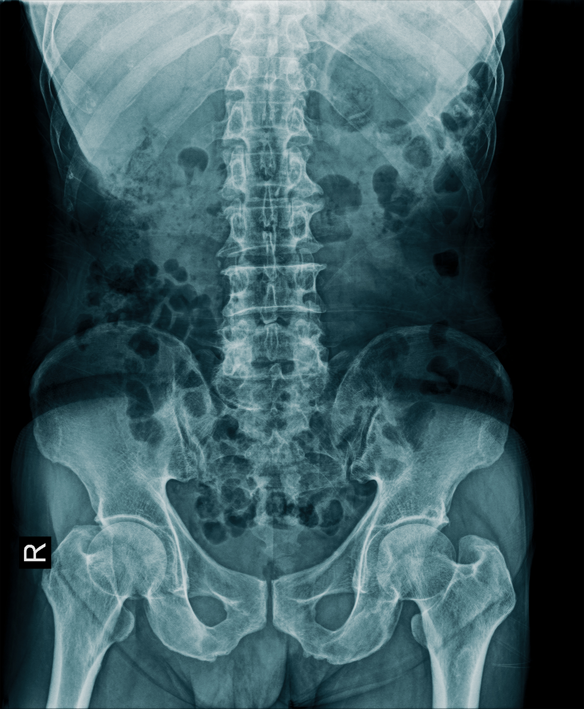

강직성 척추염

강직성 척추염은 척추와 엉덩이 관절에 염증이 생기면서 점진적으로 경직되고 통증이 발생하는 만성 질환입니다.

강직성 척추염은 치료하지 않을 경우 척추의 운동 범위가 점진적으로 감소하고, 결국에는 척추가 완전히 굳어버리는 강직 상태에 이를 수 있습니다.

이는 일상 생활의 어려움과 기능 장애를 초래하며, 장기적으로는 삶의 질을 크게 저하시킬 수 있습니다.

강직성 척추염은 척추와 골반의 관절에 염증이 생겨 시간이 지남에 따라 관절이 경직되고 통증이 지속되는 만성 염증성 질환입니다. 주로 젊은 성인에게 발생하며, 척추의 정상적인 움직임을 제한할 수 있습니다.

![]() | 허리, 엉덩이 통증이 아침에 심하고 활동 후 완화되는 경향 |

![]() | 척추의 유연성이 감소하고, 허리를 구부리거나 돌리기 어려움 |

![]() | 척추의 움직임 및 신체활동의 제한 |

![]() | 염증으로 인해 척추와 엉덩이 관절이 부풀거나 압통 |